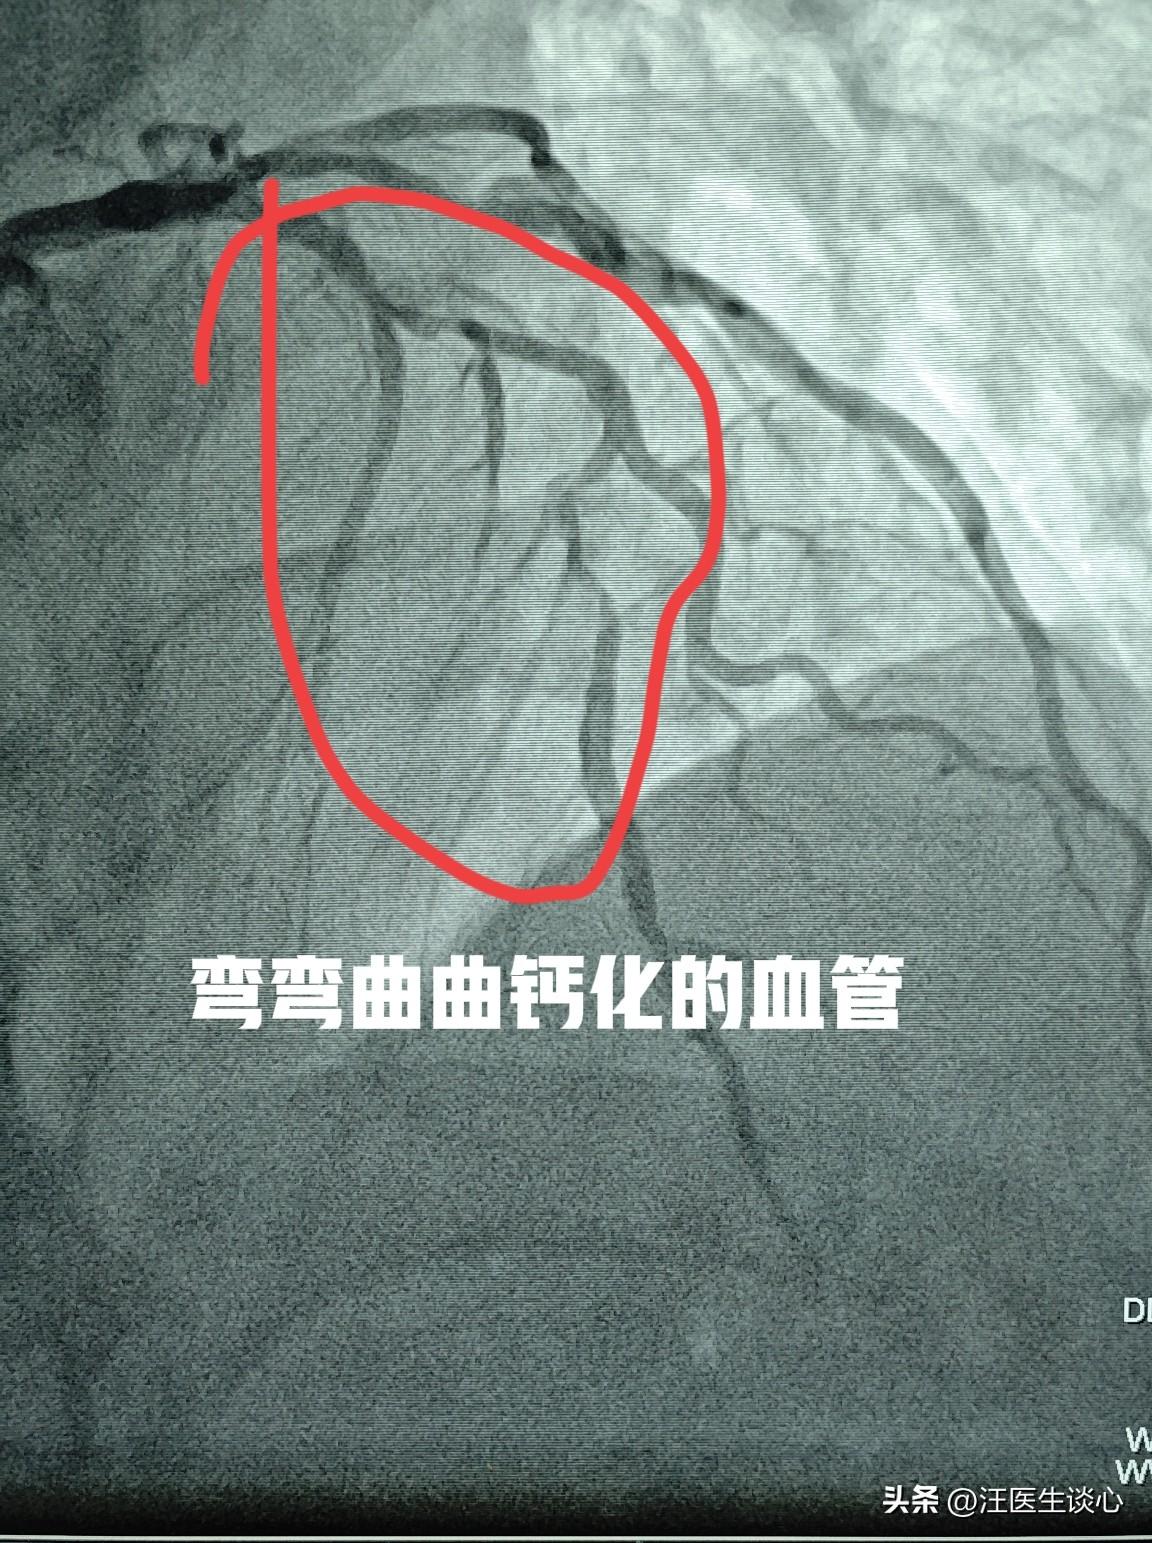

心脏血管太弯曲了,长支架过不去,只能做短的,三个变五个。 68岁男性患者因为冠心病在当地医院做了心脏造影,发现血管狭窄严重,血管呈多个S形弯曲,又有钙化,处理难度极大,就转过来治疗。 很多朋友对钙化可能不太了解。一般的血管它是有弹性的。而钙化的血管,血管壁就变得僵硬,血管壁本身是由富含弹力纤维的细胞组成。钙化以后就沉积了很多矿物质,血管就变得坚硬,像鸡蛋壳,像石头一样。直接做支架的话,在支架扩张的过程当中,血管因为缺乏弹性就会破裂,极其危险。再加上这个病人的血管弯弯曲曲的,长的支架很难通过。就像开着长长的大货车通过弯道一样,拐弯太急就无法通过。 针对这个患者,我们对这些坚硬的钙化斑块用切割球囊充分把斑块切开以后再扩张。长的支架无法通过这些弯曲的血管,于是放弃置入长的支架,改成多个短支架,串联覆盖整个病变区域。最终成功处理。